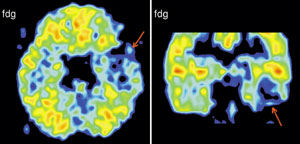

Вообще, благодаря технике позитронно-эмиссионнной томографии (или сокращенно ПЭТ), стало возможно детальное изучение одновремено всех областей мозга, отвечающих за сложные “человеческие” функции мозга. Суть метода состоит в том, что малое количество изотопа вводят в вещество, участвующее в химических превращениях внутри клеток мозга, а затем наблюдают, как меняется распределение этого вещества в интересующей нас области мозга. Если к этой области усиливается приток глюкозы с радиоактивной меткой - значит, увеличился обмен веществ, что говорит об усиленной работе нервных клеток на этом участке мозга.

А теперь представьте, что человек выполняет какое-то сложное задание, требующее от него знания правил орфографии или логического мышления. При этом у него наиболее активно работают нервные клетки в области мозга, “ответственной” именно за эти навыки. Усиление работы нервных клеток можно зарегистрировать с помощью ПЭТ косвенно, по увеличению локального кровотока в активированной зоне. (Более ста лет назад было показано, что усиленная работа нервных клеток приводит к увеличению локального мозгового кровотока в этой области.)

Области повышения локального мозгового кровотока при выполнении более сложного творческого задания по сравнению с менее творческим. Активации отмечены в правой префронтальной коре. Эти области связаны с творчеством, так сказать «в чистом виде»

В исследованиях мозговых механизмов восприятия речи по результатам ПЭТ исследования с использованием локального кровотока обнаружено, что при чтении текста основные изменения происходят в области левой височной доли (38, 22, 43, 41, 42, 40 и 38 поля), 3, 4, 6, 44, 45, и 46 полей и справа в области 22, 41, 42, 38, 1, 3, и 6 полей. Сопоставление с данными других исследователей позволяет соотносить некоторые из этих результатов с процессами запоминания, чтения слов, понимания смысла. Появилась возможность выделить области, связанные с восприятием смысла и запоминанием текста, от областей, которые связаны с обработкой отдельных слов. Эти результаты коррелируют с полученными ранее с помощью анализа нейронной активности. Были также подтверждены результаты, полученные при исследовании нейронной активности, о вовлечении в обеспечение речи, наряду с классическими зонами, участков мозга, расположенных в других областях. При исследовании мозгового обеспечения речи картированы области коры мозга человека, участвующие в обеспечении различных стадий анализа орфографиче-ских и синтаксических характеристик. Показано, что медиальная экстрастриарная кора вовлечена в обработку орфографической струк-туры слов; значительная часть левой верхневисочной коры (зона Вернике) наиболее вероятно участвует в произвольном семантическом анализе, и менее вероятно - обработке синтаксической структуры; нижняя лобная кора левого полушария является звеном системы вербального семантического анализа, ее возможное участие в синтаксической обработке ограничено обработкой словоформ и функциональных слов, но не порядка их следования в предложении; в определение синтаксической структуры фразы на основе анализа порядка следования слов вовлечена передняя часть верхневисочной коры. На основе анализа мозгового кровотока удалось показать, что, когда человеку предъявляется связный текст даже без необходимости его читать,- задание было считать появления определенной буквы - мозг тем не менее существенно, более интенсивно вовлекается в обработку лингвистических характеристик стимулов, что выражается в активации определенных зон, чем при предъявлении с тем же заданием тех же слов, но несвязанных, перемешанных в случайном порядке.

Мозговая система непроизвольной синтаксической обработки.

Проекции на латеральные поверхности полушарий мозга областей активации (p < 0,01), полученных в условиях поиска буквы в связном тексте, предъявляемого бегущей строкой, в сравнении с аналогичной задачей при предъявлении синтаксически

Активация мозга в условиях обработки текста.

Области локального повышения функциональной активности нервной ткани, полученные в условиях задачи на понимание читаемого текста, по сравнению с задачей поиска буквы в бессмысленной буквенной последовательности. Показаны проекции зон значимых (p < 0,0001) активаций на три ортогональных плоскости (вид справа, сзади и сверху, соответственно, в верхнем ряду справа и слева, в нижнем ряду - слева). Внизу справа показаны проекции кортикальных латеральных активций в левом полушарии на реконструированную поверхность левого полушария «стандартного» мозга.

Активации мозга в покое.

Области повышенной функциональной активности (p < 0,0001) в состоянии спокойного бодрствования с закрытыми глазами по сравнению с прослушиванием связного текста. Для примера показаны два горизонтальных ПЭТ- «среза» на уровнях, обозначенных красными линиями на схеме «стандартного» мозга в стереотаксической системе координат.